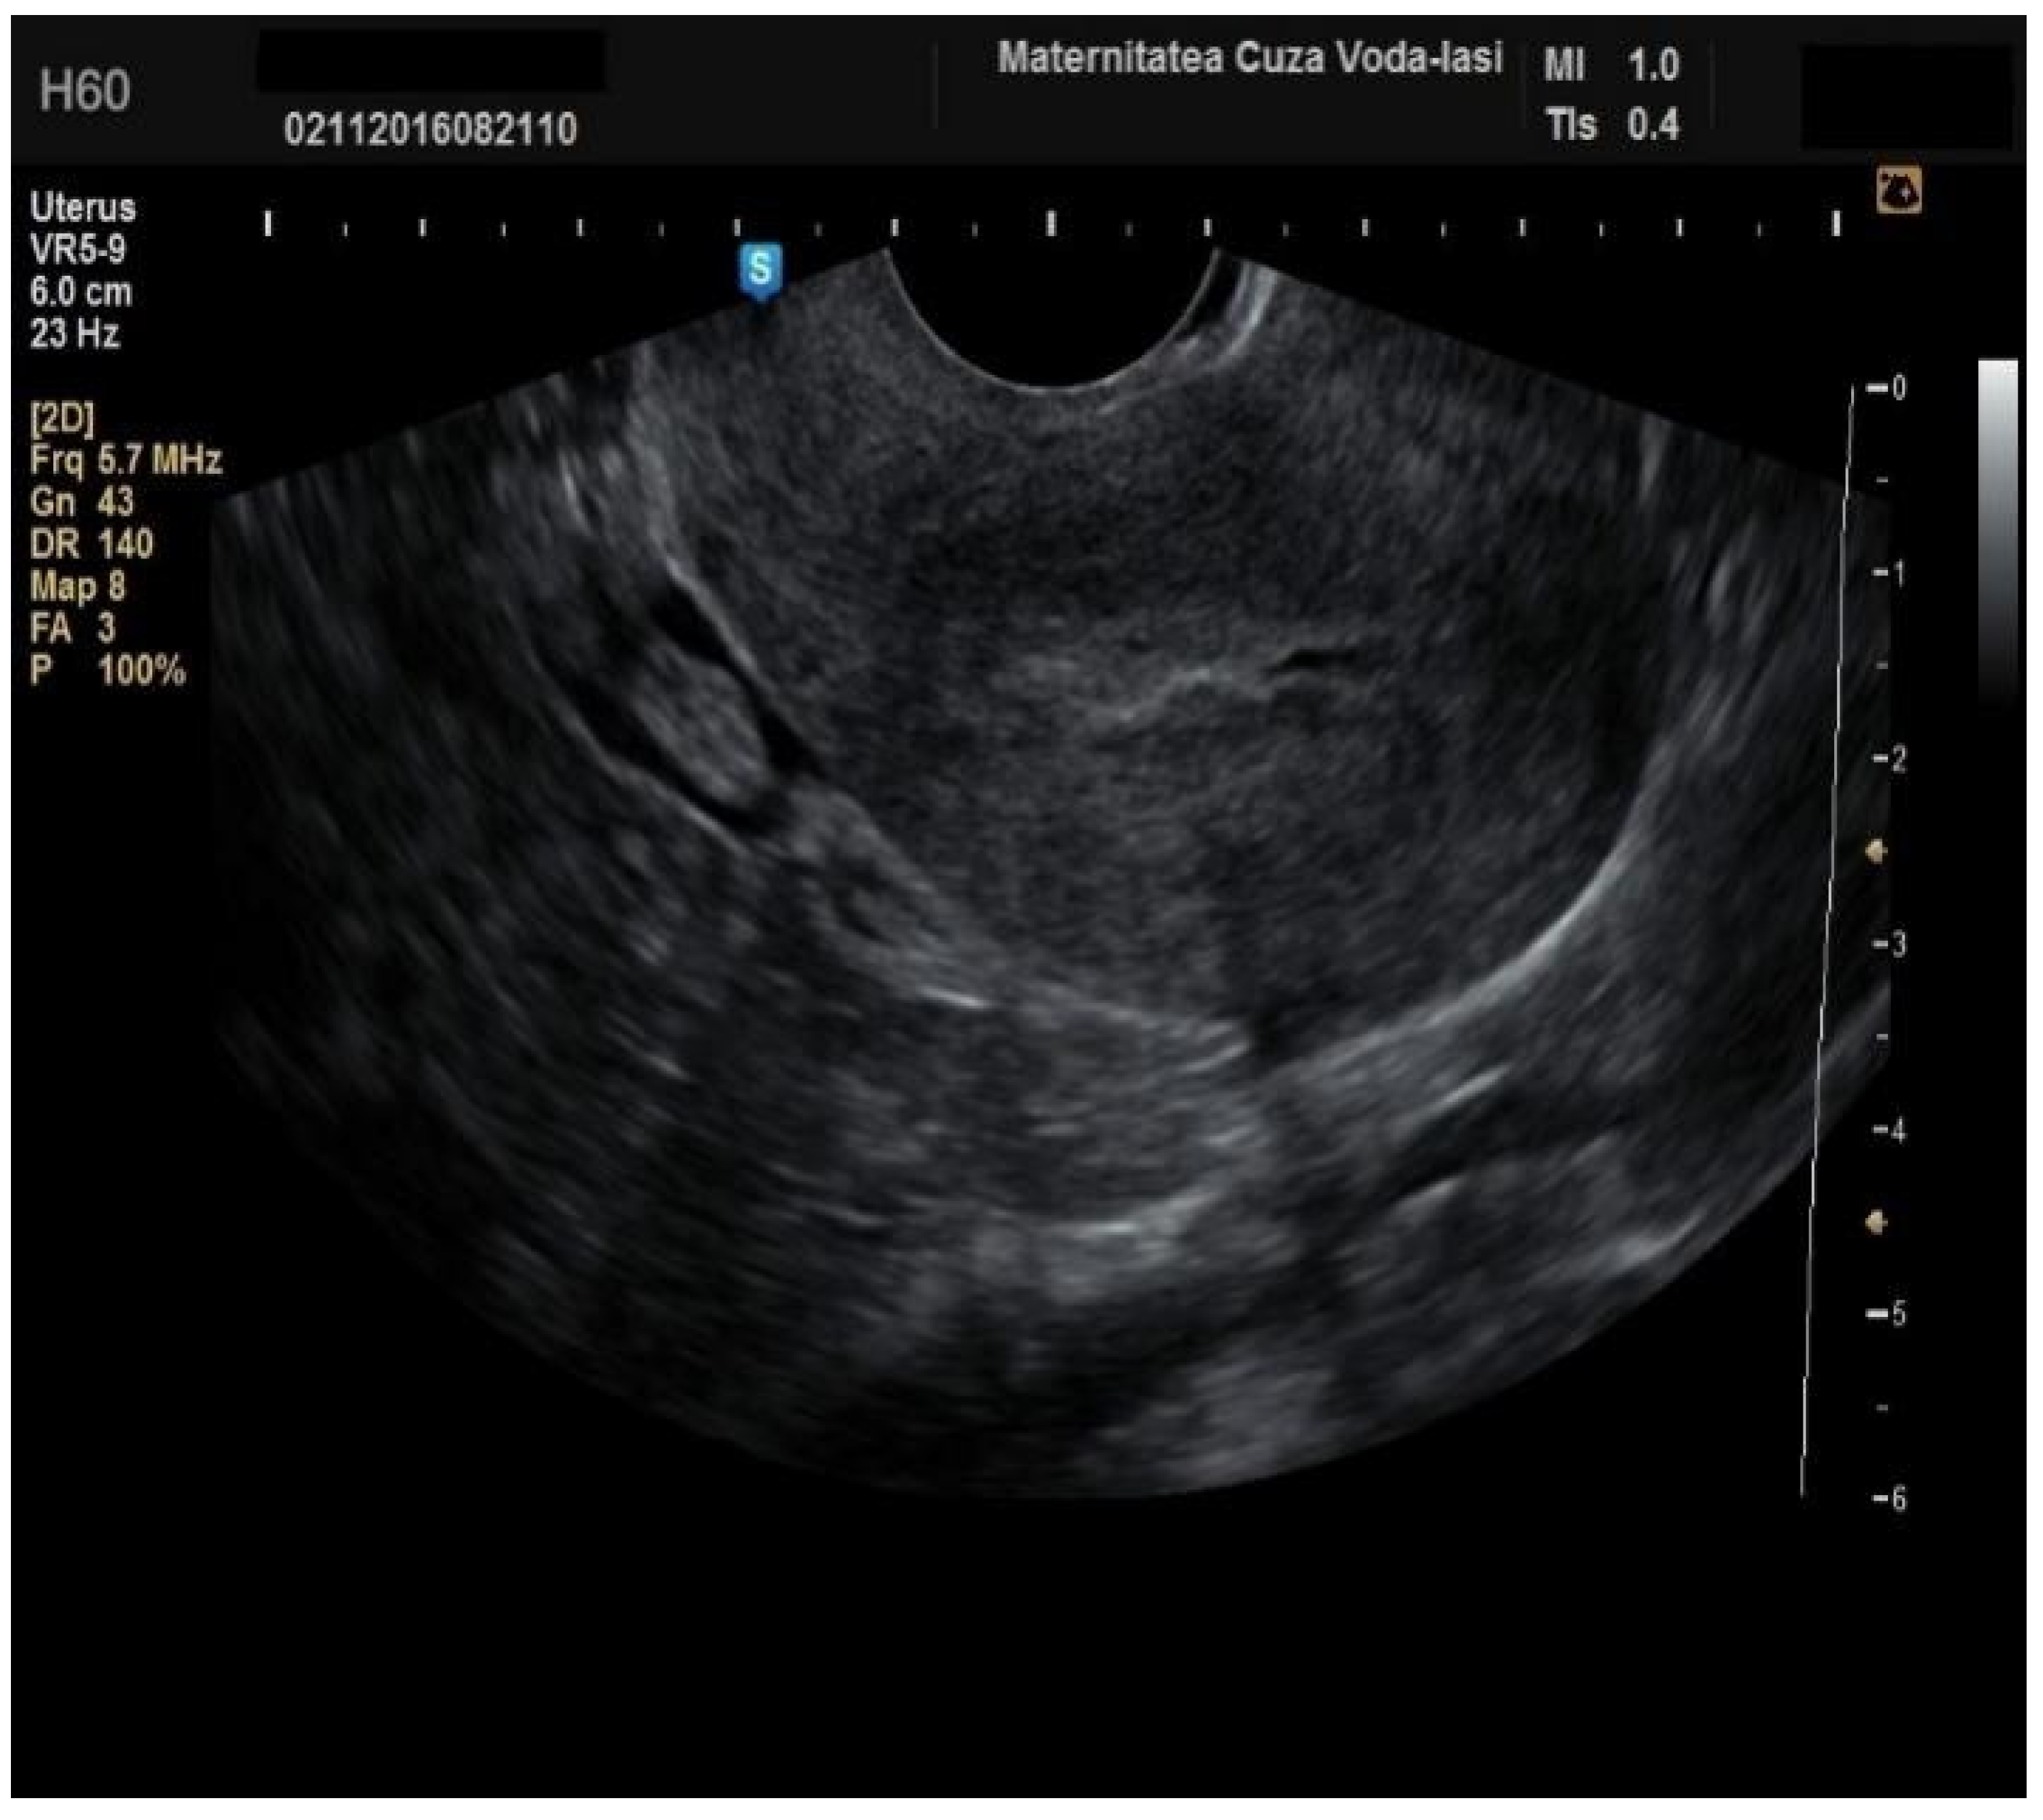

Figure 2. Ultrasonographic imaging of endometrial cancer.

The average endometrial thickness, as measured by transvaginal ultrasonography, was found to be 18.02 ± 10.94 mm (range: 5–64 mm). Malignancy was identified in 22.84% of cases with uterine cavity findings. The mean endometrial thickness for women diagnosed with endometrial cancer was 24.49 ± 13.33 mm (95% confidence interval [CI]: 14.34 to 35.16), (Figure 2), whereas those with other pathologies had a mean thickness of 16.10 ± 9.37 (95% CI: 13.14 to 18.57), (Figure 3), with statistical significance (p = 0.028). When endometrial thickness was used as a standalone variable to build a model for estimating the risk for endometrial malignancy it demonstrated the highest AUC with a value of 0.682 (95% CI: 0.452–0.912). A cut-off threshold of 26 mm for endometrial thickness yielded a sensitivity of 62.5% and a specificity of 89% (Figure 4).